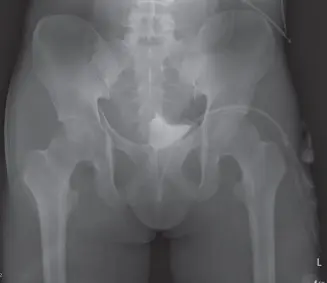

صورة توضيحية لـ خلع الورك الرضحي: دليل شامل للمريض مع الأستاذ الدكتور محمد هطيف في صنعاء

صورة سريرية تظهر تشوهًا واضحًا في الورك بعد الخلع الخلفي.

• الأشعة السينية (X-rays):

• تُعد الأشعة السينية للورك والحوض (الوضع الأمامي الخلفي والوضع الجانبي عبر الطاولة) هي الفحص الأولي والأكثر أهمية لتأكيد تشخيص خلع الورك.

• تُظهر الأشعة السينية بوضوح خروج رأس عظم الفخذ من تجويف الحُق وتُساعد في تحديد اتجاه الخلع (خلفي أو أمامي).

• يمكن أن تكشف أيضاً عن الكسور الكبيرة المصاحبة، مثل كسور الحُق أو كسور عنق الفخذ.